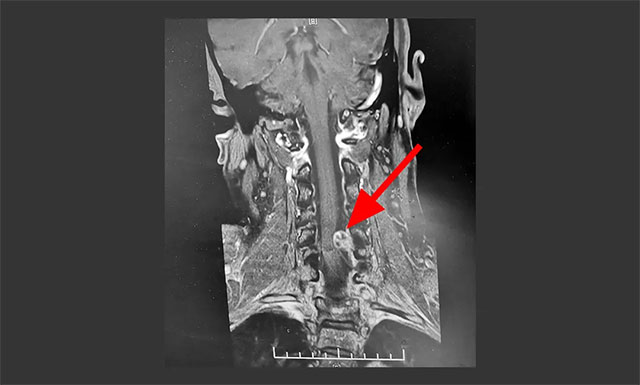

▲ MR显示肿瘤位于椎管左侧髓外硬膜下

结合患者症状及之前相关影像检查,有着多年临床经验的潘仁龙主任怀疑患者可能为脊髓相关病变。急行颈椎MRI平扫+MRA+MRM示,颈椎序列整齐、曲度存变直;平颈5椎体水平,椎管左侧髓外硬膜下见一“哑铃状”异常信号灶,椎管内灶矢横高径约8*10*15mm,跨越左侧颈5-6椎间孔向外生长;毗邻脊髓受压右偏。颈5-6椎间盘脊髓变性、伴轻度右后突出;颈3-4、颈4-5椎间盘变性、膨出;颈椎退行性改变。